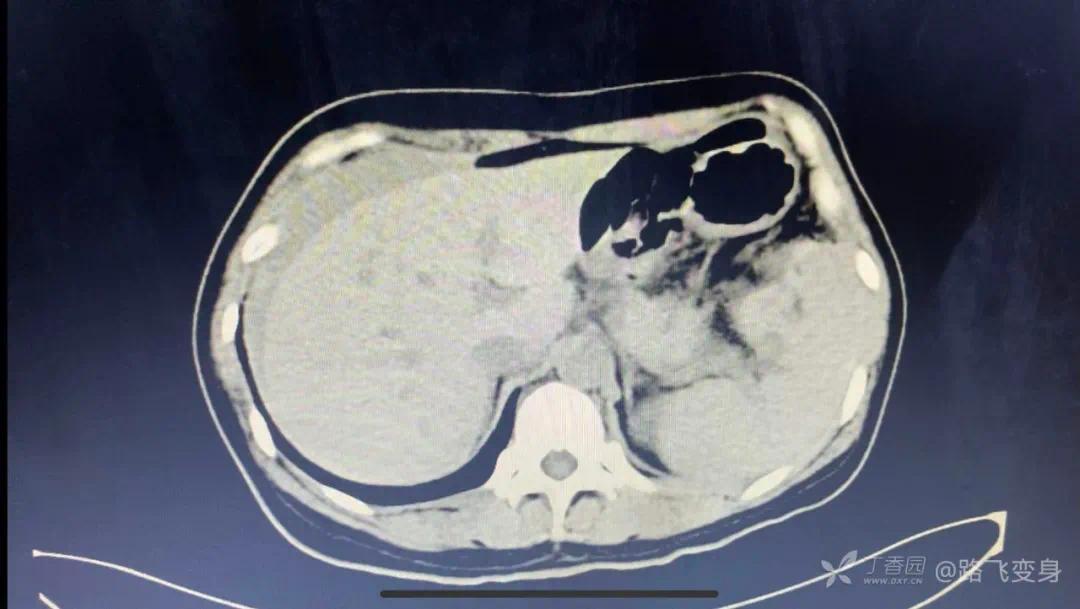

病人出现「休克」症状,没有办法只有准备手术,术前常规行全腹部 CT 检查,如下:

CT 发现明显异常。可以和下面第一次急诊 CT 视频做对比。